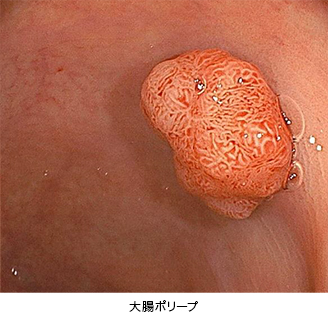

● ポリープ

当院で採用している富士フイルム社製のレーザー内視鏡は、高精細なハイビジョン画像、画像強調機能(BLI)および最大135倍の光学拡大機能を持ち、微細な病変を詳細に観察することができます。また、腸管壁のカーブに沿ってスムーズにスコープが曲がる「カーブトラッキング技術」を搭載しており、苦痛の低減と検査時間の短縮を実現しています。

拡大内視鏡などで詳細な観察を行い、切除すべきかどうか判断します